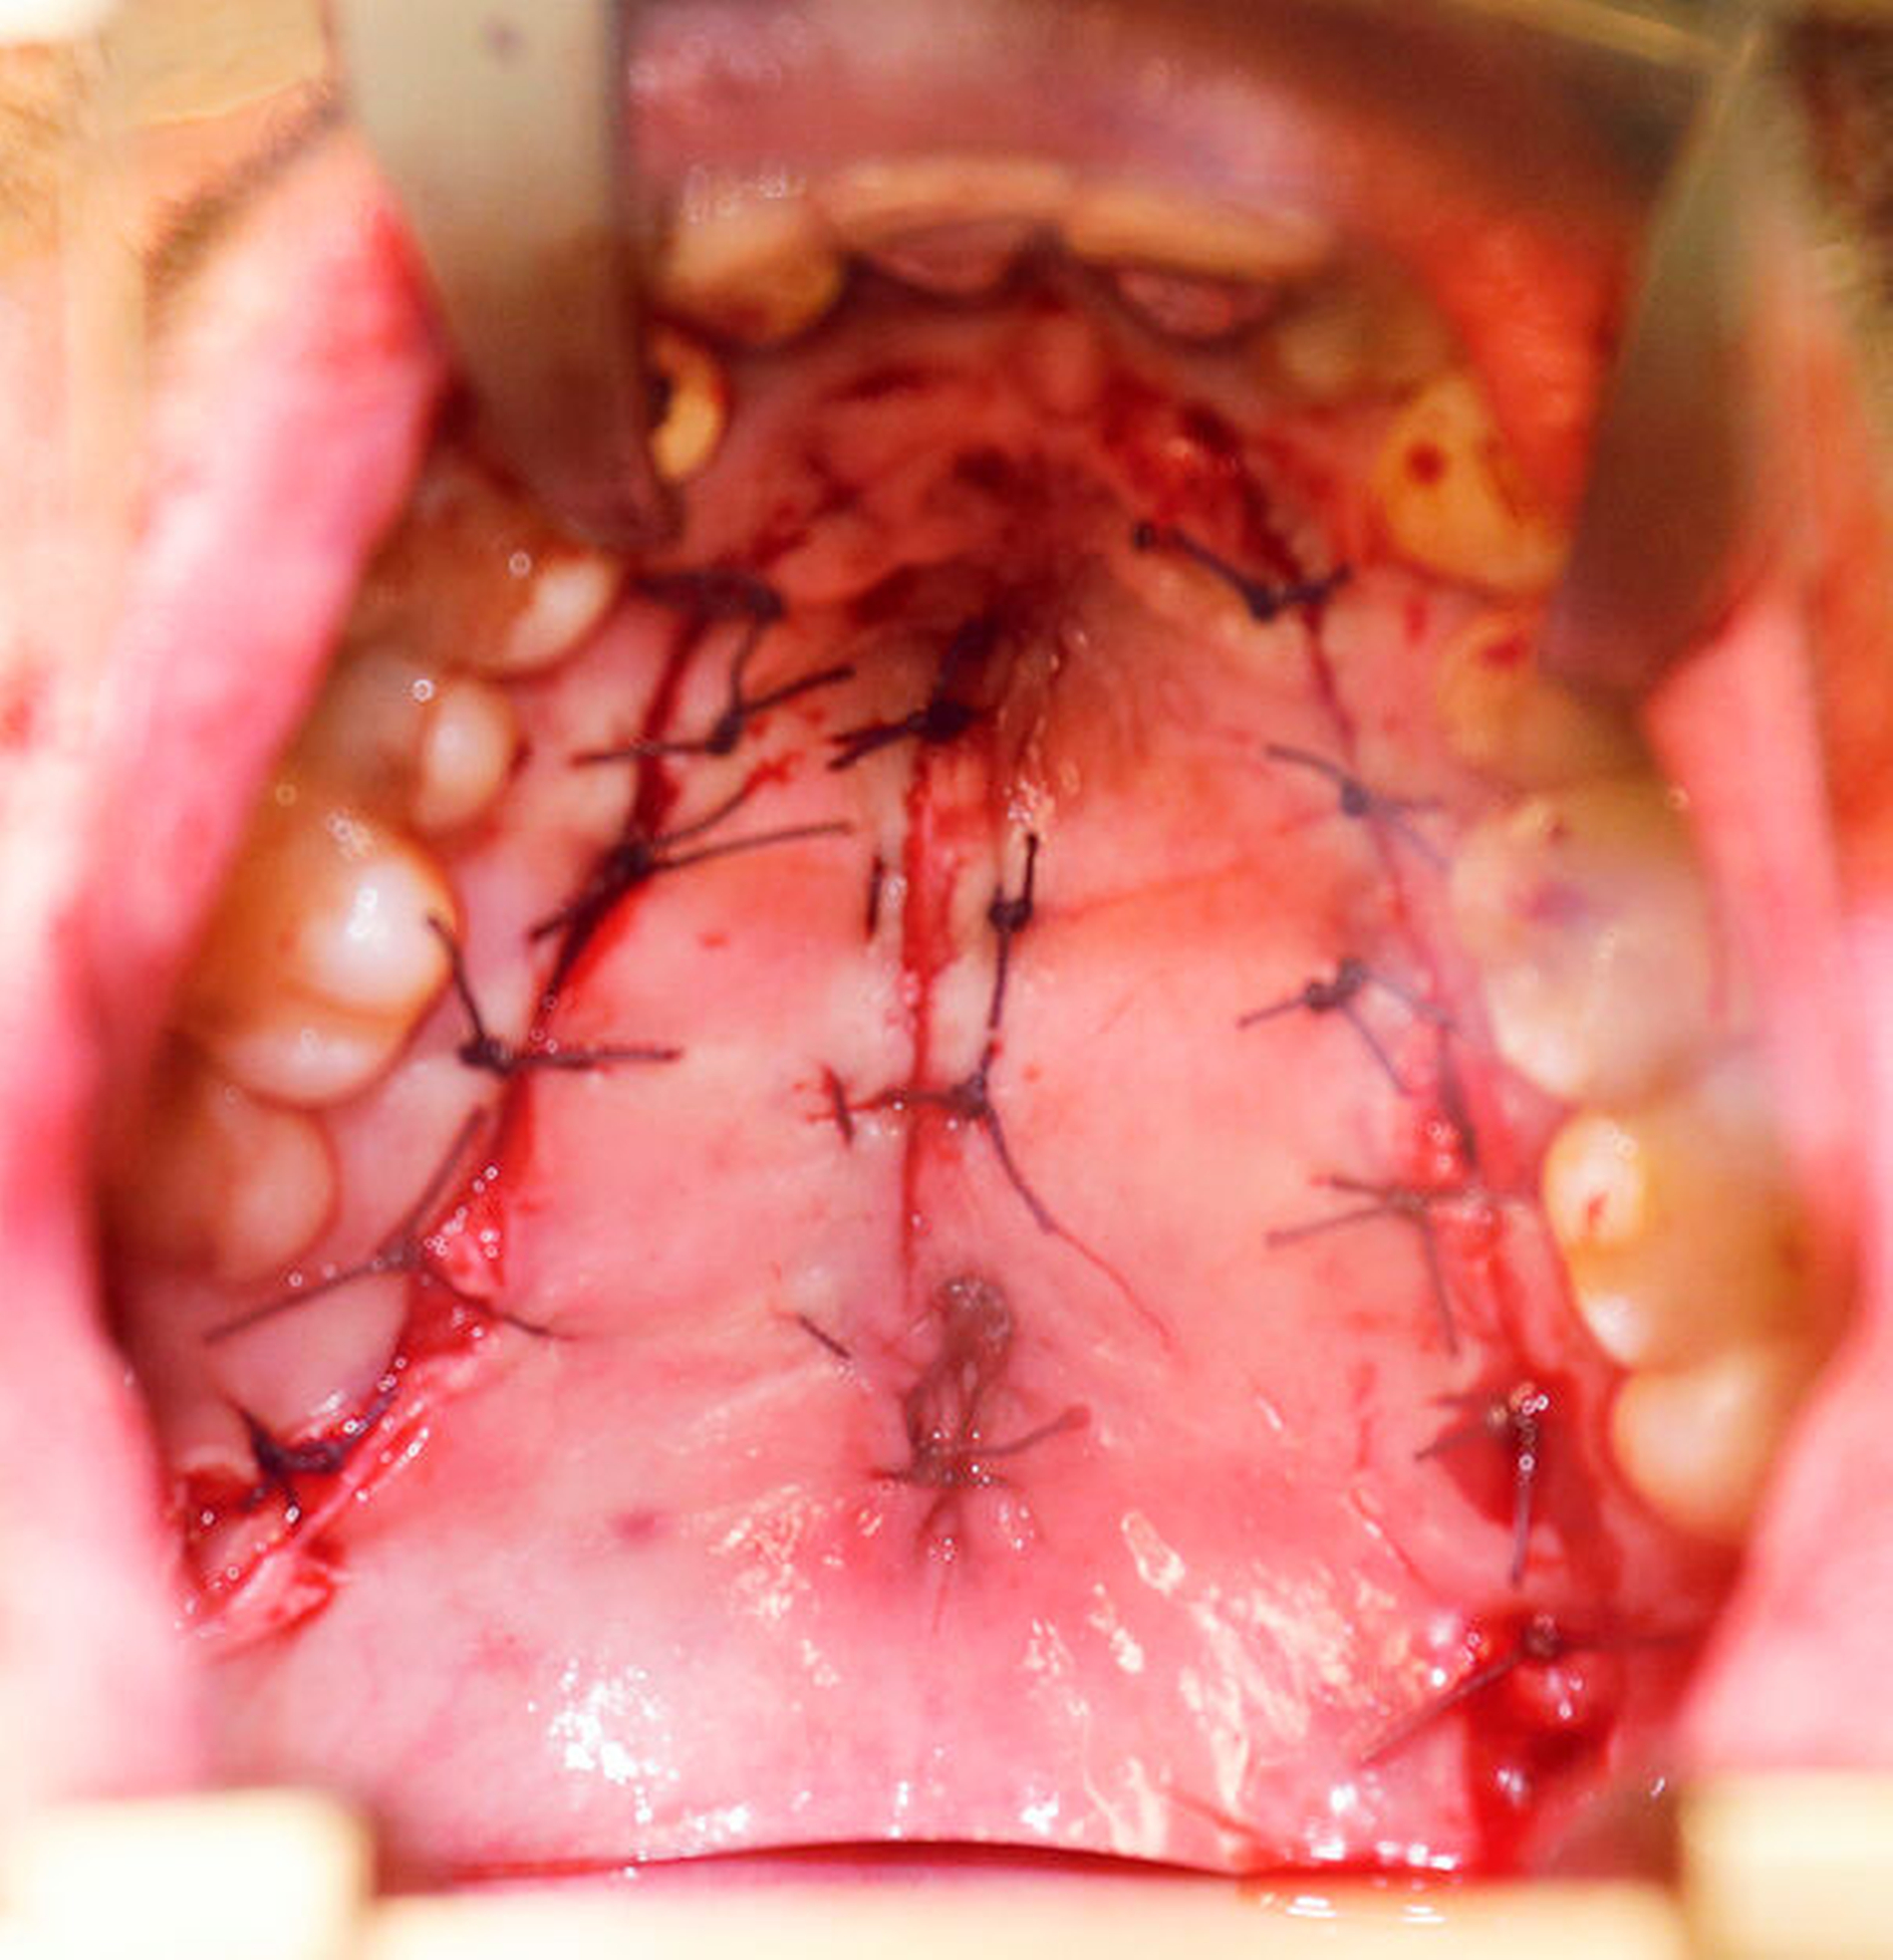

Nach vier Monaten konnten die internistische Therapie unter Remission bei einer deutlichen Besserung des Allgemeinzustands ausgeschlichen und der operative Defektverschluss geplant werden. Die zweischichtige Palatoplastik führten wir in oraler Intubationsnarkose unter stationären Bedingungen durch (Abbildungen 5–7).

Am dritten postoperativen Tag wurde der Patient mit stadiengerechter Wundsituation in die ambulante Nachsorge entlassen. Es wurde flüssig-breiige Kost für zwei Wochen empfohlen, sowie ein striktes Schnäuz- und Nikotinverbot für drei Wochen ausgesprochen. Die intraoralen Fäden wurden am 14. postoperativen Tag entfernt.